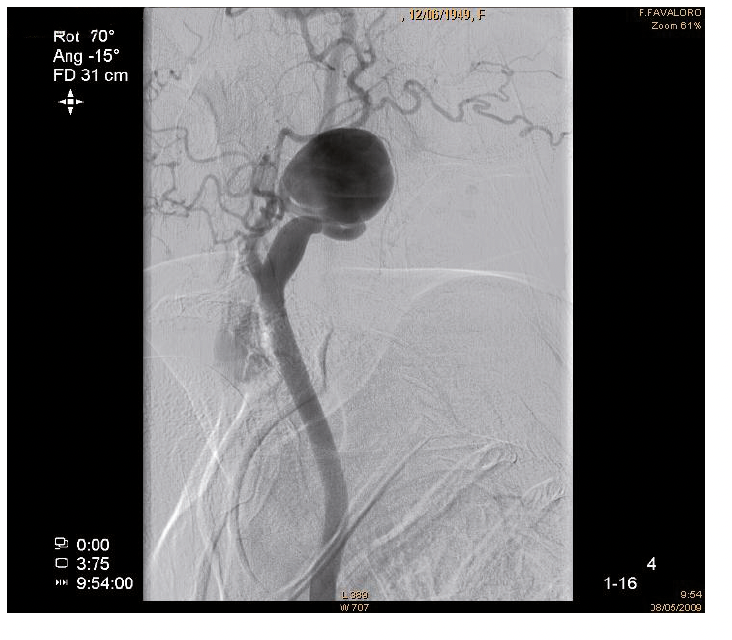

Aneurisma carotídeo

IMÁGENES EN CARDIOLOGÍA